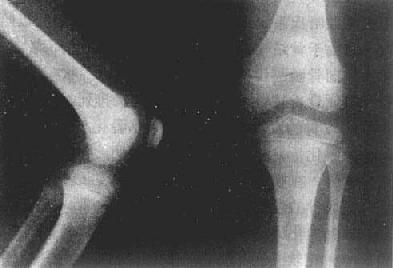

儿童正常膝关节

图2-1-2 儿童正常膝关节

X线上,由于软骨、关节囊都是软组织密度,不能显示,所以,相对骨端之骨性关节面间呈半透明间隙,称之为关节间隙(joint space)。因此,X线所见关节间隙包括了关节软骨及其间的真正微小间隙和少量滑液。两个相对骨端的骨性关节面光滑整齐,相距匀称,间隙清晰,宽度均匀(图2-1-4)。关节间隙的宽度因部位和年龄而异。

正常成人膝关节

图2-1-4 正常成人膝关节

股骨下端胫骨上端的骨性关节整齐,间隙清晰,宽度均匀